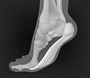

• ÁÖ¸» ³ªµéÀÌ Áß ¹ß¹Ù´ÚÀÌ ¿í¾À?¡¦'À̰Í' ÀǽÉÇØ¾ß

ÁÖ¸» ³ªµéÀÌ Áß ¹ß¹Ù´ÚÀÌ ¿í¾À?¡¦'À̰Í' ÀǽÉÇØ¾ß

û·®ÇÑ °¡À»À» Áñ±â±â À§ÇØ ÁÖ¸»ÀÌ¸é ³ªµéÀÌ¿¡ ³ª¼­´Â À̵éÀÌ ¸¹´Ù. ƯÈ÷ °¡º­¿î Á¶±ëÀ̳ª °ñÇÁ µîÀÇ ¾ß¿Ü ½ºÆ÷Ã÷¸¦ Áñ±â´Â »ç¶÷µéÀÌ ´Ã°í ÀÖ´Ù. ±×·¯³ª Æò¼Ò¿¡ ¿îµ¿À» ²ÙÁØÇÏ°Ô ÇÏÁö ¾Ê¾Ò°Å³ª ¿îµ¿·®ÀÌ Àû¾ú´ø »óȲ¿¡¼­ ¹«¸®ÇÏ°Ô °ÉÀ¸¸é ¹ß¹Ù´Ú¿¡ ÇǷΰ¡ ÁýÁßÀûÀ¸·Î Ãà..